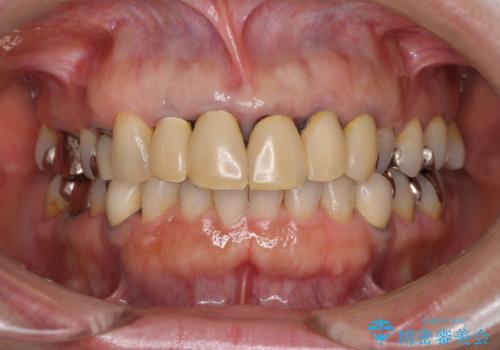

自然で透明感のある前歯になると同時に、歯茎付近の黒ずみや隙間も改善でき、患者様には大変満足していただきました。

- 保険診療で装着した前歯のクラウンの変色を気にして来院された患者様です。

また、裏打ちに主に銀を用いた金属材料を使用するため、金属自体が黒くなったり、イオンとなり溶け出したりして、歯肉ラインが黒くなってしまうことがあります。